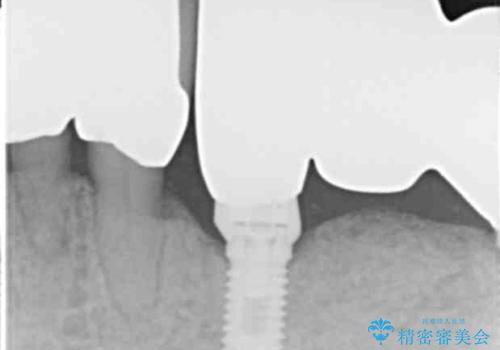

再生療法から1年後リエントリー手術により骨の再生を確認し、骨外科処置(骨を平らにして歯周ポケットの根本的な改善を図る処置)を行ったのち、連結補綴を行いました。

骨吸収と動揺が著しい前歯1本(左下1)のみ抜歯しております。

再生療法と骨外科処置により、歯周ポケットは全周2mm以下に改善されました。

保存が難しいと思われた歯を残すことができ、患者様にご満足頂けました。